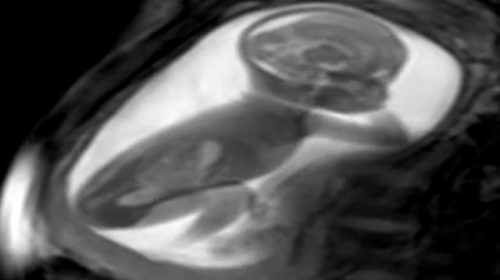

Naučnici su uspjeli da naprave trodimenzionalni prikaz srca bebe u maminom stomaku. Precizne mape srca nerođenih beba prave se od snimaka magnetne rezonance na osnovu kojih zatim softver izrađuje 3D model srca.

Bebino srce prvo se snima magnetnom rezonancom iz nekoliko uglova kako bi se dobio niz dvodimenzionalnih fotografija. Pošto je srce bebe u tom stadijumu veoma malo i kuca nevjerovatno brzo, a beba se u stomaku pomjera – fotografije su mutne.

Zato sofisticirani kompjuterski softver fotografije se prilagođava brzini kucanja bebinog srca, zatim spaja dvodimenzionalne slike i pravi 3D prikaz srca.